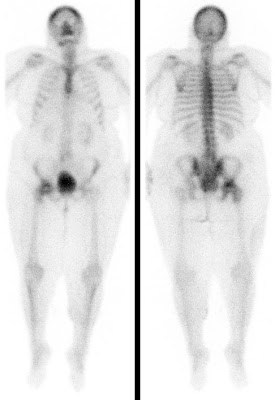

Bei der Skelettszintigraphie werden schwach radioaktiv markierte Phosphatkomplexe verabreicht, die zunächst im Blut durch den Körper zirkulieren und im Verlauf von 2-3 Stunden ausreichend in den Knochen eingebaut werden, so dass dann der Knochenstoffwechsel abgebildet werden kann.

Es bestehen die Möglichkeiten, gleich nach Verabreichung der Phosphatkomplexe die Durchblutung zu untersuchen und auf den Spätaufnahmen den Knochenumbau zu beurteilen. Bei der Skelettszintigraphie gibt es keine Unverträglichkeitsreaktionen auf die verabreichten Radiopharmaka. Im Gegensatz zu vielen Röntgenkontrastmitteln sind die verwendeten Radiopharmaka auch nicht nierenschädlich.

Die Hauptfragestellungen bei der Skelettszintigraphie betreffen die Feststellung evtl. Knochenmetastasen bei Krebserkrankungen und die Unterscheidung von primär entzündlichen vs. primär degenerativen Gelenkerkrankungen, also rheumatischen Grunderkrankungen mit Skelettbeteiligung vs. (aktivierten) Arthrosen.

Darüber hinaus ist die Skelettszintigraphie häufig auch bei der Abklärung unklarer Knochenschmerzen sehr hilfreich, etwa zur Feststellung evtl. Knochentumoren, von Prothesenlockerungen, einer Osteomyelitis, von Frakturen, von Knocheninfarkten etc.